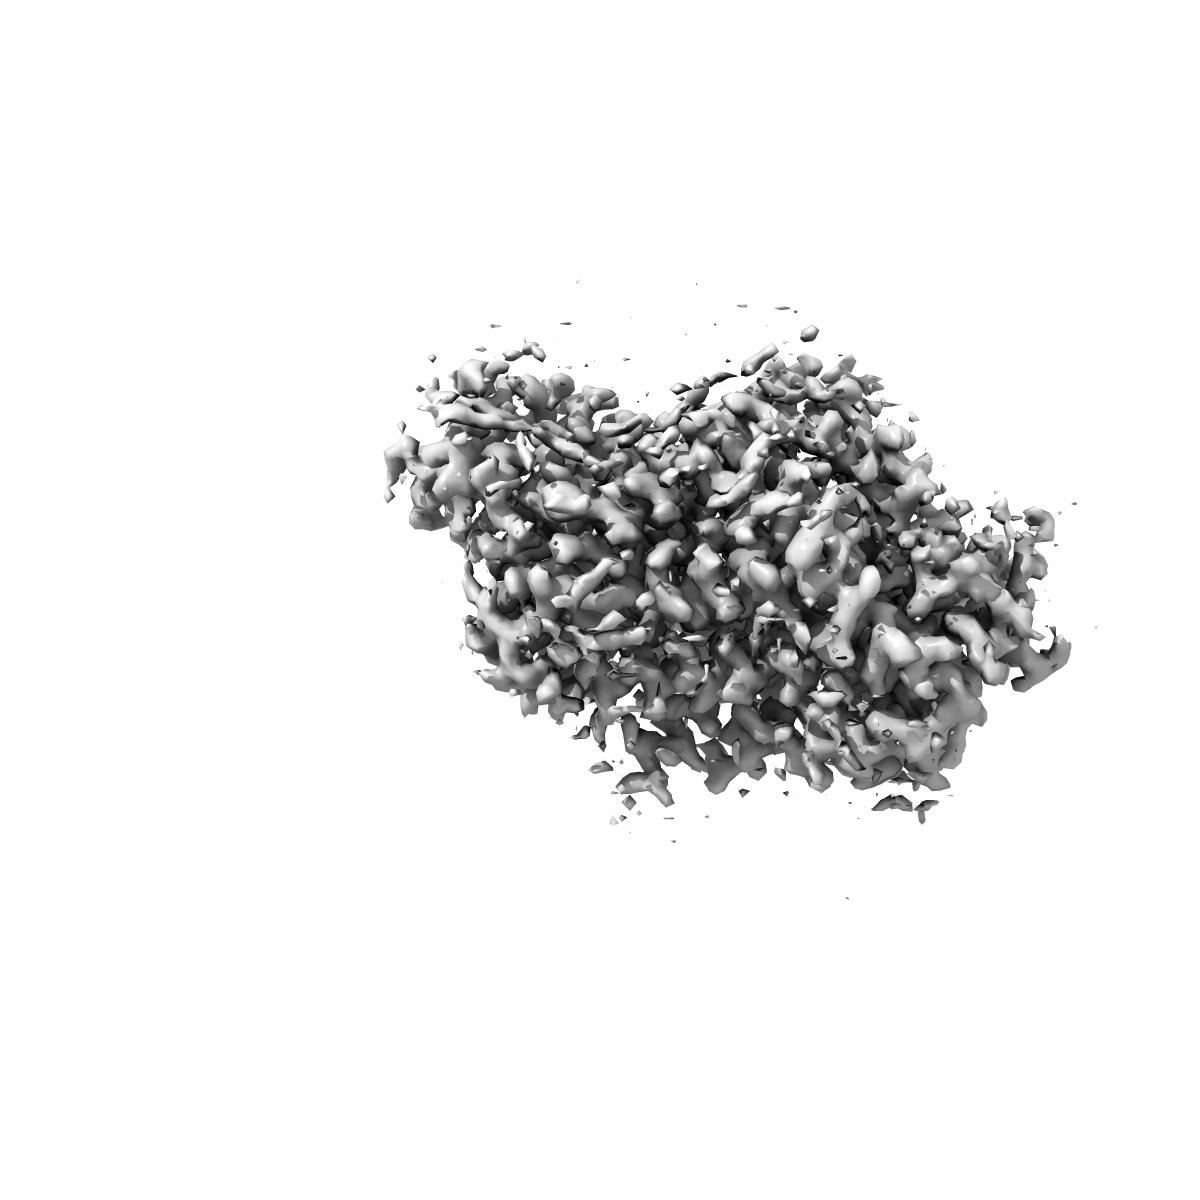

Cryo-EM structure of human norepinephrine transporter NET in the presence of the antidepressant desipramine in an inward-open state at resolution of 2.5 angstrom.

Single-particle2.5 Å

Fitted models: 8hfi

Molecular basis of human noradrenaline transporter reuptake and inhibition.

(2024) Nature , 632 , 921 - 929